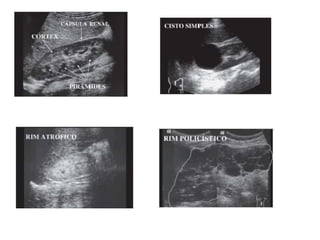

Ultra-sonografia

• Indicações:

 Obstruções do sistema coletor

 Nefrolitíase

 Distinção entre lesões císticas e sólidas

 Avaliação vascular

 Biópsia renal

• Limitações: ar, osso e tecido adiposo.

Ultra-sonografia • Indicações:  Obstruçõesdo sistema coletor  Nefrolitíase  Distinção entre lesões císticas e sólidas  Avaliação vascular  Biópsia renal • Limitações: ar, osso e tecido adiposo.